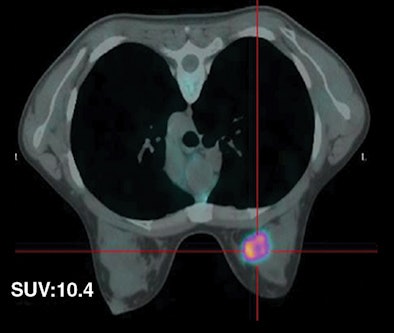

| Fifty-five-year-old woman with ductal infiltrating adenocarcinoma measuring 15 mm in maximum transverse diameter. Axial fused PET/CT images obtained with patient in prone position at time point 1 (above) and time point 2 (below) show corresponding standard uptake values. All images courtesy of the American Roentgen Ray Society. |